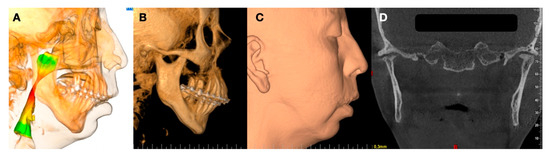

1.3. Clinical Conditions Related to Use of TMJ Replacement

- Volume and Size Augmentation of the Mandibular Condyle

- Volume and Size Reduction of the Mandibular Condyle

- Malformations, Pathology, or Trauma of the Mandibular Condyle